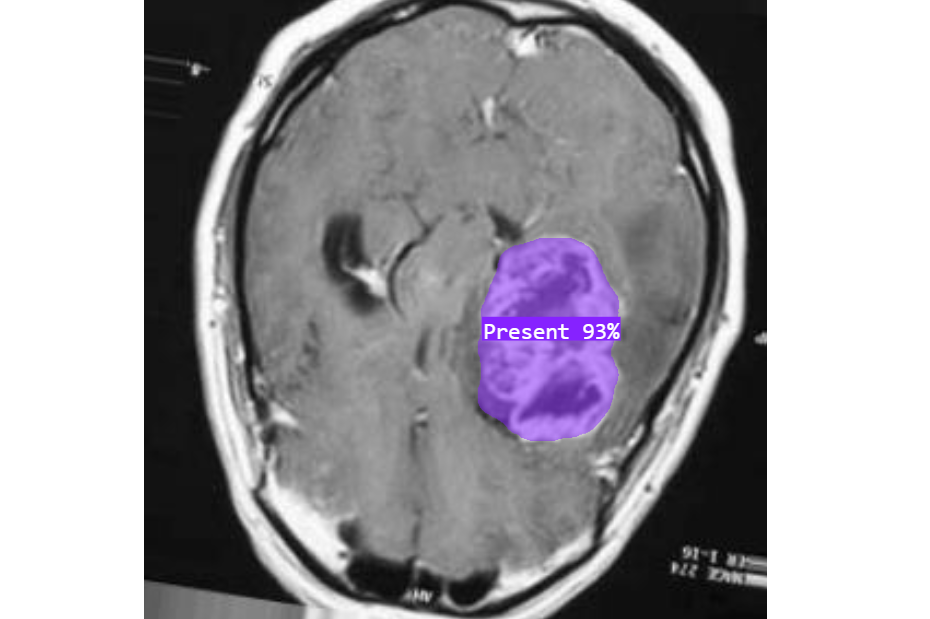

Image Segmentation

Vertex AI helps in training segmentation model that helps in highly detailed analysis of shapes, boundaries, and regions of interest. Examples:

- Outlining tumors in MRI scans in healthcare.